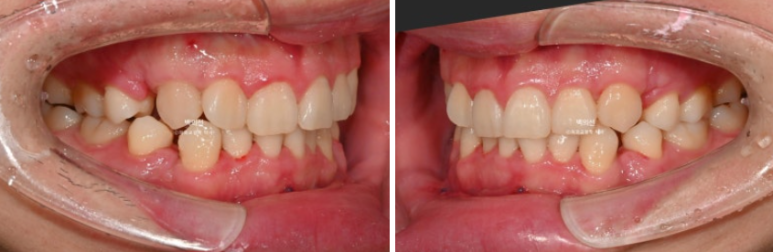

교합 배열 모든 게 좋습니다만

25.03

아직 미세하게 남아있는 공간을 없애고자 추가장치를 제작하기로 했습니다.

25년 4월부터 8월까지 5개월간 14개 장치를 모두 낀 후 모습입니다.

25.08

남아있던 공간은 추가장치로 깔끔히 없어졌습니다.

총 치료기간은 10개월, 재제작 1회 입니다.